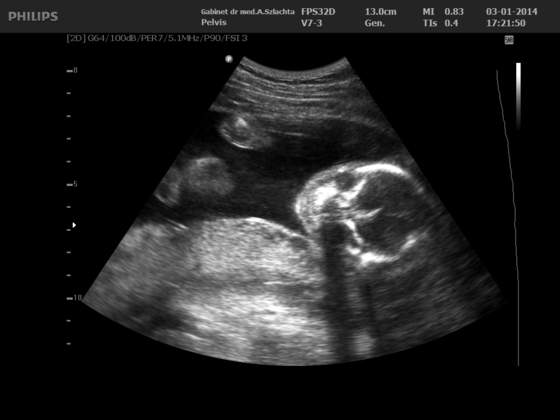

Byłam dziś na wizycie 3d/4d tzn na połówkowym.. I ciesze się bardzo, że mój gin dał mi skierowanie... A więc moja dziewczynka okazała się CHŁOPCEM na 100% Mały waży 562 gramy, wszystko dobrze, tylko Pani doktor nie podobała się prawa nerka i podejrzewa torbielowatość.. Może się mylić i sama to przyznała, więc załatwi nam wizytę na konsultacje do Poznania na Polna, we wtorek mam się dowiedzieć kiedy mam się tam udać.. Nóżki tak zaciskał, aż raz pokazał, co tam chowa i w końcu wiemy wszystko na 100% . Tak się kręcił, że ciężko było zdjęcie zrobić, ale cosik widać

A i termin z ostatniej miesiączki 3.05, a wg usg 30 kwiecień..